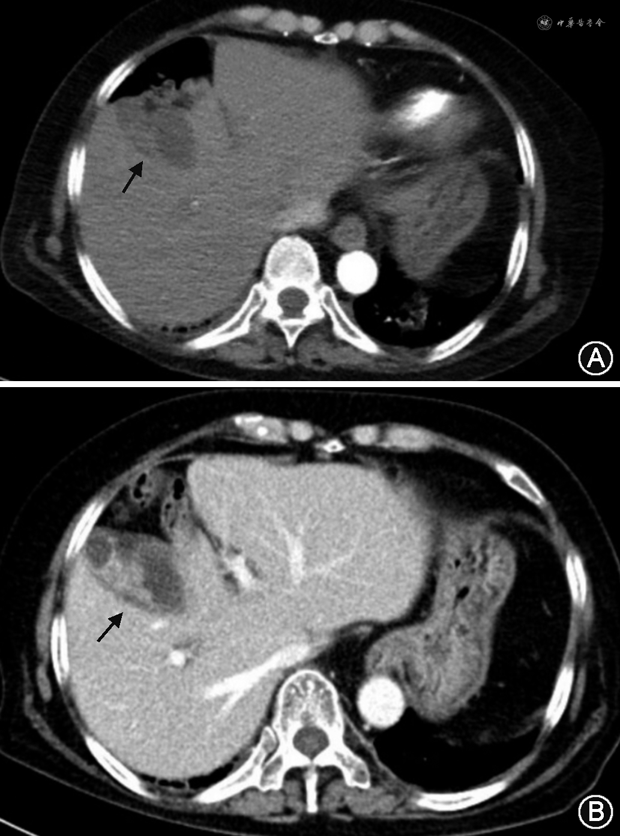

入院次日患者诉头晕、呼吸困难,测 SpO2 92%(未吸氧),血气示pH 7.45,氧分压 67 mmHg,二氧化碳分压32 mmHg,乳酸 4.4 mmol/L,心肌肌钙蛋白(cTnI)正常范围,N末端B型钠尿肽原(NT-proBNP)281 pg/ml,超声示双侧股浅静脉至胫后静脉起始段血栓形成。CT肺动脉造影(CTPA)示右肺动脉主干及双肺多发分支栓塞(图2),左肺下叶团片影伴小空泡(图3);胆囊底壁局限性缩窄(图4A)。监测患者血压显著降至85/63 mmHg,持续时间>15 min,心率90 次/min,呼吸25 次/min,意识清晰,考虑为急性肺栓塞,肺栓塞严重程度指数(PESI)评分至少为100分,简化的肺栓塞严重程度指数(sPESI)评分至少1分,血流动力学不稳定,危险分层为高危。转入监护病房后血压逐渐回升至125/66 mmHg,予普通肝素持续静脉泵入,维持APTT 50 s左右,呼吸困难缓解,3日后改为依诺肝素钠4 000 U每12小时皮下注射。

2020年11月11日转入呼吸内科继续治疗,皮肌炎方面维持甲泼尼龙20 mg/d口服。完善肌炎抗体谱示:抗伴抗小泛素样修饰物活化酶(SAE)抗体、抗Ro-52抗体阳性。腹部超声示脂肪肝,胆囊体部囊壁增厚;双大腿MRI示肌肉萎缩;肌电图示肌源性损害。考虑皮肌炎为肿瘤相关性皮肌炎可能性大,原发灶未明。多学科讨论认为患者肺部病变有恶性可能,但血供丰富不宜穿刺活检;而胆囊形态异常结合CA19-9明显升高,恶性病变可能性更大。进一步行腹部增强CT(图4B),见胆囊形态欠规则,壁不均匀增厚伴异常强化,考虑恶性可能;肝可疑低强化结节,转移待除外;胰头后方多发肿大淋巴结。PET-CT示胆囊底壁不规则增厚恶性可能性大,胰头后方淋巴结转移可能性大,肝脏未提示;左肺下叶片影炎性病变可能性大。综上,患者胆囊来源的恶性病变可以解释病情全貌。基本外科认为目前肿瘤所致症状及合并症突出,虽不能除外局部转移,但行胆囊切除手术方有根治机会。